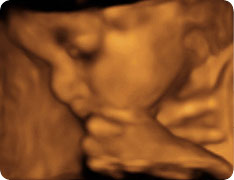

3d УЗИ видео зевающего малыша в утробе

Ребенок зевает и потягивается в утробе

В наше время познакомиться с малышом можно еще до его рождения, ведь на 4d узи при беременности можно запечатлеть видео внутриутробной жизни вашего пузожителя. Представляете, каково ему будет взглянуть на это лет, эдак, через 15?